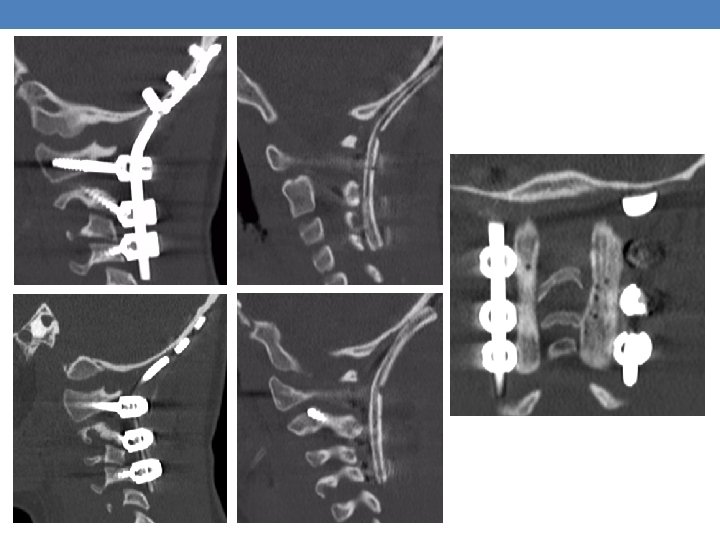

Case 1 A 6 -year-old female with no prior medical history was brought to the emergency room after a high energy car accident, complaining: • Paraplegia • Weakness (0/5) of the right upper limb • Severe neck pain • Respiratory distress The imaging showed an Atlanto-Occipital Dissociation

C 1, C 2 fixation with Goel. Harms technique and C 4 transarticular screw insertion